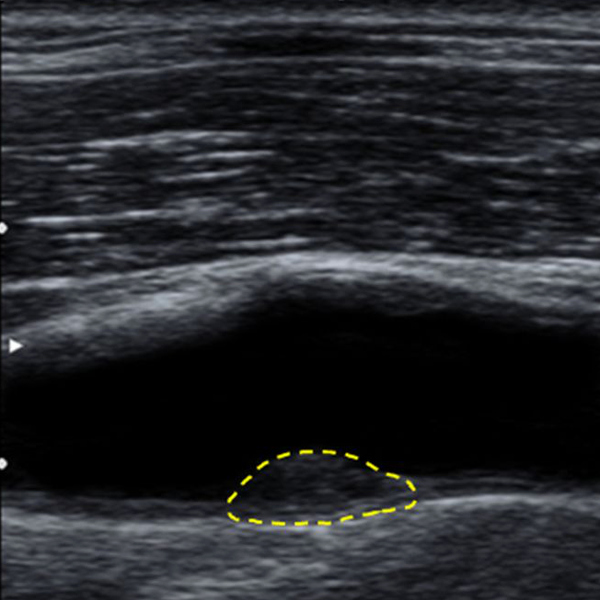

Hjärt- och kärlsjukdomar är den största folksjukdomen i Sverige idag. Åderförkalkning, ”ateroskleros” är den främsta orsaken till hjärt-kärlsjukdom.

Åderförkalkning kan byggas upp i kärlen under lång tid innan det ger några symtom.